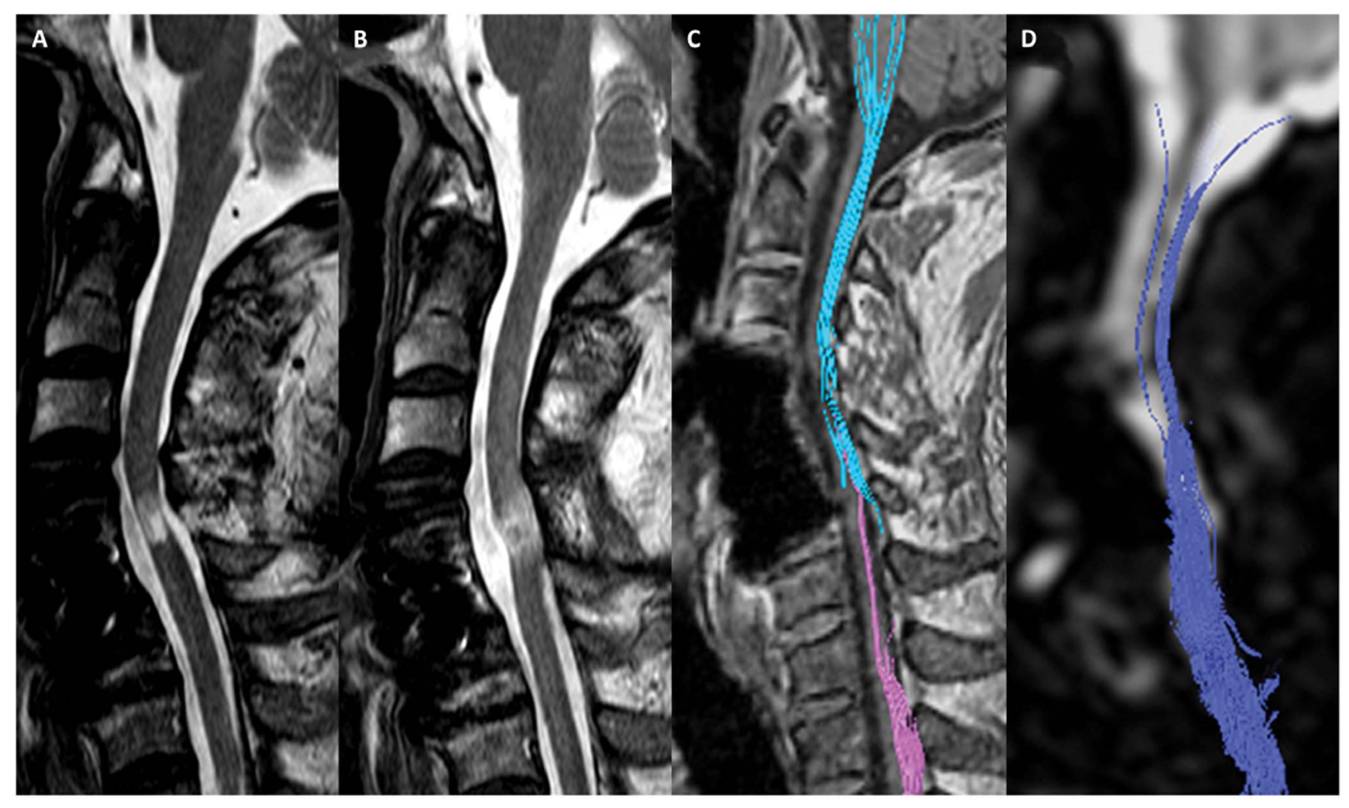

이어 “그러나 줄기세포치료제를 단회 투여했음에도 불구하고 호전된 환자의 척수 MRI 및 DTI 검사 결과 척수손상 부위에서 줄기세포치료 전에는 없던 섬유의 연속성(fibercontinunity)이 확인되는데 이는 줄기세포치료로 인한 신경재생 효과로 판단할 수 있다"고 말했다.

[환자의 DTI검사결과다. 줄기세포치료제 투여하기 전(A와C)에 비해 투여 후 6개월이경과한 후(B와 D)에는 끊어진 척수신경이 재생되었음을 확인할수 있다